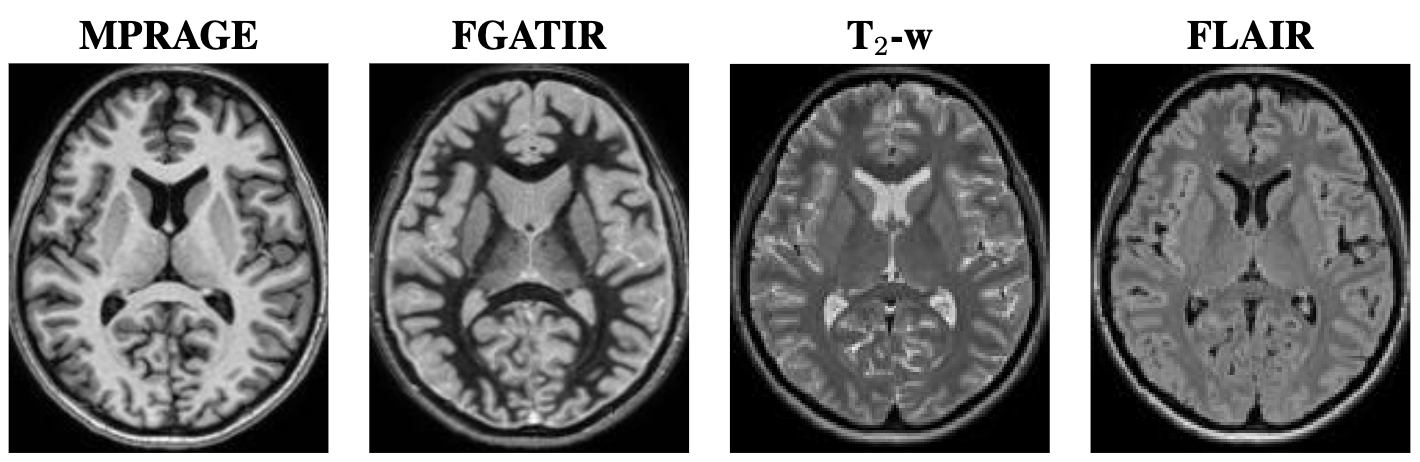

Our training dataset consists of four brain MR image contrasts that have been acquired for 23 subjects. These contrasts include MPRAGE, FGATIR, T2-w, and FLAIR. Example images of these four contrasts are shown in Fig. 3. The MPRAGE and FGATIR images are acquired with the same imaging parameters (TR = 4,000ms, echo time = 3.37ms, flip angle = 66^{\circ}, and magnetic field strength = 3 Telsa) except for their inversion times (TIs), which are TI = 1,400ms for the MPRAGE and TI = 400ms for the FGATIR. For training the networks described in Sec. 2.5, we used a 5-fold cross validation. We divided our 23 subjects into 14 training subjects, 4 validation subjects, and 5 testing subjects. For the 5th-fold, only 3 testing subjects were used to allow each subject to be tested once. The validation set was used to monitor the loss during training and for early stopping.

Refer to caption

Figure 3: Example images from the same subject, from left to right, are the MPRAGE, FGATIR, T2-w, and FLAIR.